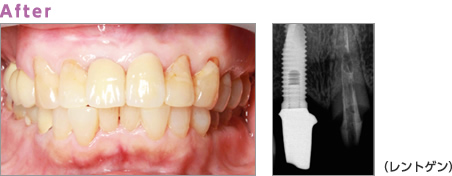

Implant Treatmentインプラント治療

インプラント治療

“第2の永久歯、手にいれてみませんか?”

歯が抜けたところにチタン製の人工歯根を埋入し、その人工歯根にセラミックの歯を装着する補綴方法です。両隣の歯に頼らずに歯を入れることができます。

また、一本の歯として利用できるため、健康寿命や健口寿命にも大きく関わります。また、歯や歯ぐきとの相性も良く、お身体にとっても優しい治療です。

症例2

Before:右上の前歯が破折のため抜歯となりました。

After:抜歯した歯をインプラントにして審美性の回復を行いました。

治療費用

インプラント(CT・診断・手術) ¥240,000/歯+上部補綴

ジルコニアセラミック ¥100,000/歯